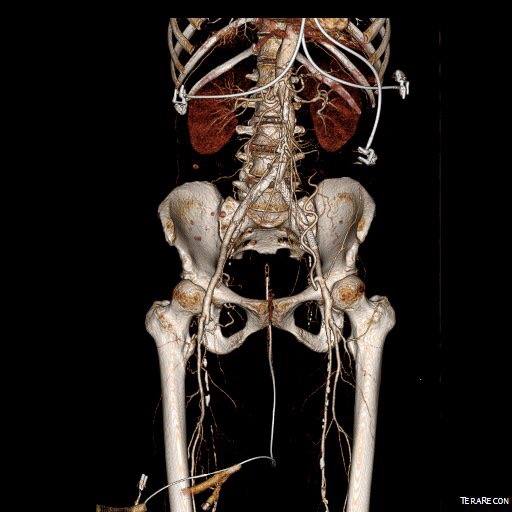

CTA (pictured above and below) showed a 5.1cm infrarenal AAA with an hourglass shaped neck with moderate atherosclerosis in the neck, an occluded left common iliac artery with external iliac artery reconstitution via internal iliac artery collaterals, and a right external iliac artery occlusion with common femoral artery reconstitution. There was calcified right common femoral artery plaque.

There was diffuse bilateral iliac atherosclerotic plaque with occlusion of the right common femoral artery and left common and external iliac artery. The 3DVR (three dimensional virtual reality) reconstruction image below shows this as well as the abdominal and pelvic wall collaterals feeding the legs around the occluded iliofemoral system.

The 3DVR reconstruction images are shown below, with the comparison to preop shown in the first image of this blog entry: